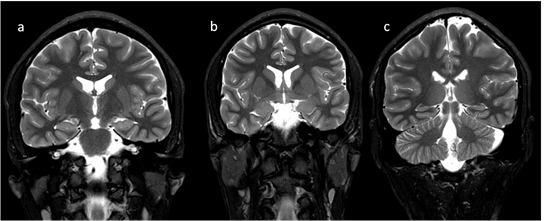

2 Brain Mri Pattern In Biotin Thiamine Responsive Basal Ganglia Download Scientific Diagram

Teaching Neuroimages Mri Findings Of Biotin Responsive Basal Ganglia Disease Before And After Treatment Neurology

Biotin Responsive Basal Ganglia Disease Neuroimaging Features Before And After Treatment American Journal Of Neuroradiology